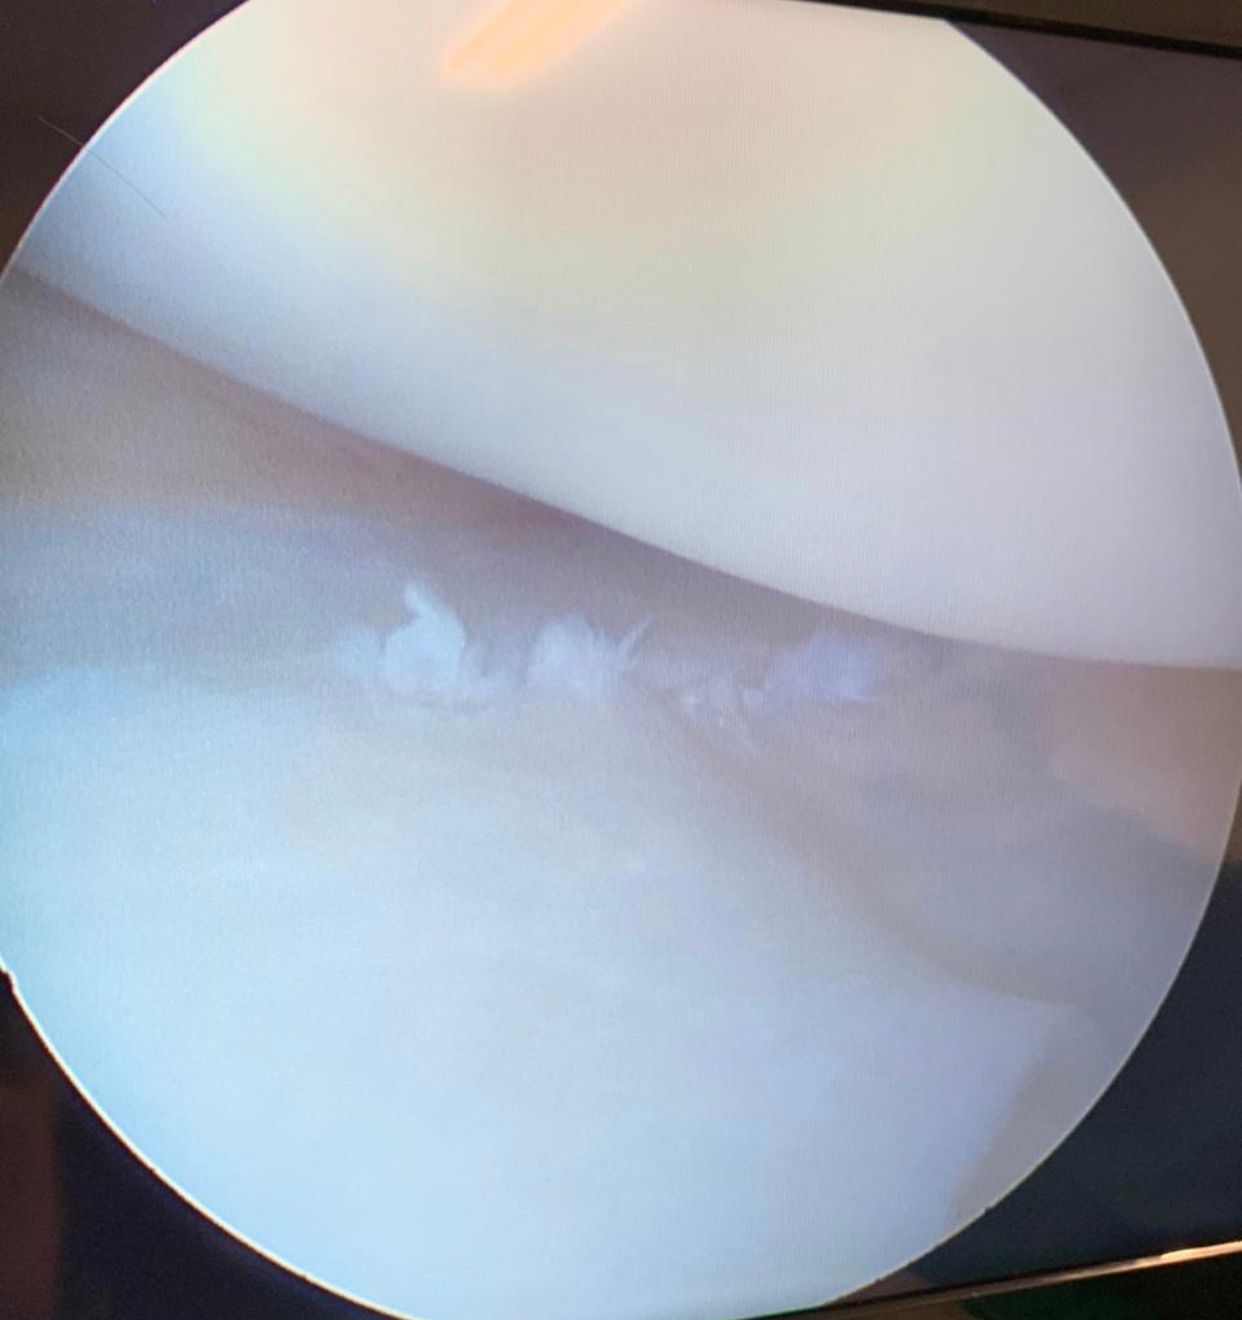

• Cirurgia do Joelho

• Lesões do joelho: meniscos

Artroscopia Cirurgica Do Joelho individualmente

Videoartroscopia individualmente

Artroscopia individualmente